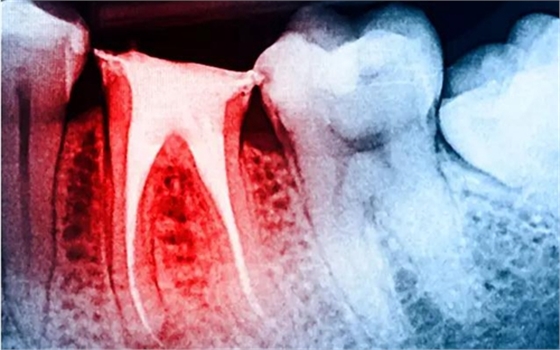

大量研究表明:與活髓牙相比,根管治療后牙體組織的強(qiáng)度、韌性以及硬度等力學(xué)性能均無明顯改變,牙髓活力對(duì)牙齒的生物力學(xué)性能的影響十分有限;而齲損組織、舊充填物和后續(xù)的治療修復(fù)過程造成的冠根部牙體組織的喪失才是引起牙齒抗折強(qiáng)度降低的主要原因。牙體強(qiáng)度與剩余牙體組織的量密切相關(guān),牙體組織缺損愈多,抗折力降低愈明顯。

根管治療后最終修復(fù)策略的制定取決于剩余牙體組織的量,以及牙齒在牙弓中的位置,同時(shí)還要兼顧功能與美學(xué)的恢復(fù)?;颊邔?duì)菌斑的控制也會(huì)對(duì)修復(fù)預(yù)后產(chǎn)生影響。對(duì)于齲病的易感人群,冠方封閉不良是使微生物滲入根管內(nèi),導(dǎo)致根管治療失敗的最可能因素。此外,患牙周病的患者,如果患牙斷面位于齦下,那么修復(fù)失敗的可能性就會(huì)增高。